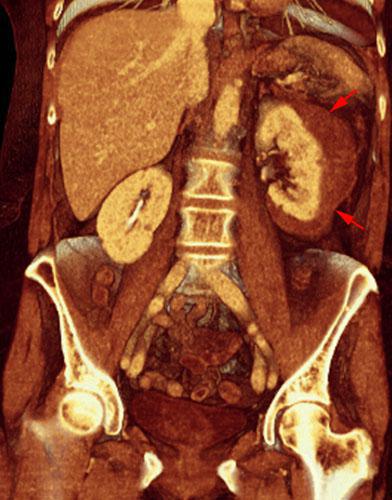

Estallido renal